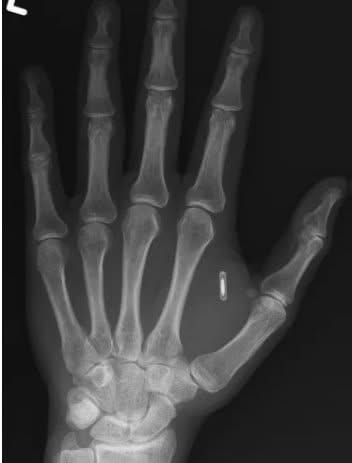

О своей проблеме Ван, выступающий под псевдонимом Zi the Mentalist, рассказал в соцсетях, приложив рентгеновский снимок. На нём отчётливо виден белый контур микрочипа, застрявшего в мягких тканях между большим и указательным пальцами.